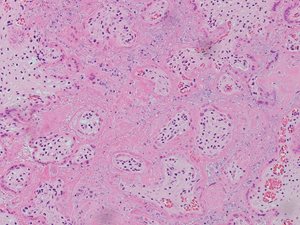

In both cases, placental histology showed extensive diffuse intervillous and perivillous fibrin deposition with widespread associated villous infarction and hemorrhage (Figs. 2a and 2b).

Fig. 2a. Extensive intervillous and perivillous fibrin deposition with associated villous infarction, 10X (Case 1).

Fig. 2b. Extensive intervillous and perivillous fibrin deposition with associated villous infarction, 20X (Case 1).